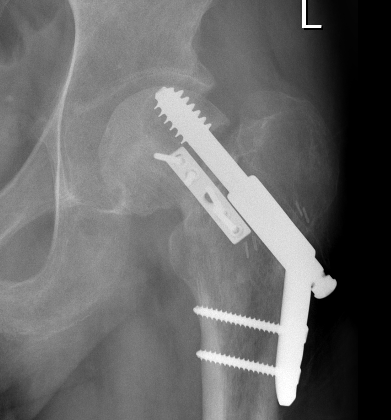

Fixation

DHS /Cannulated screws / FNS

Unstable fracture - augment with a medial buttress plate on inferior neck

Medial buttress plate